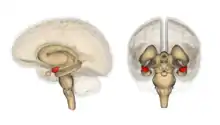

Frontal and side view of amygdala

Amygdala along with other subcortical regions, in glass brain.